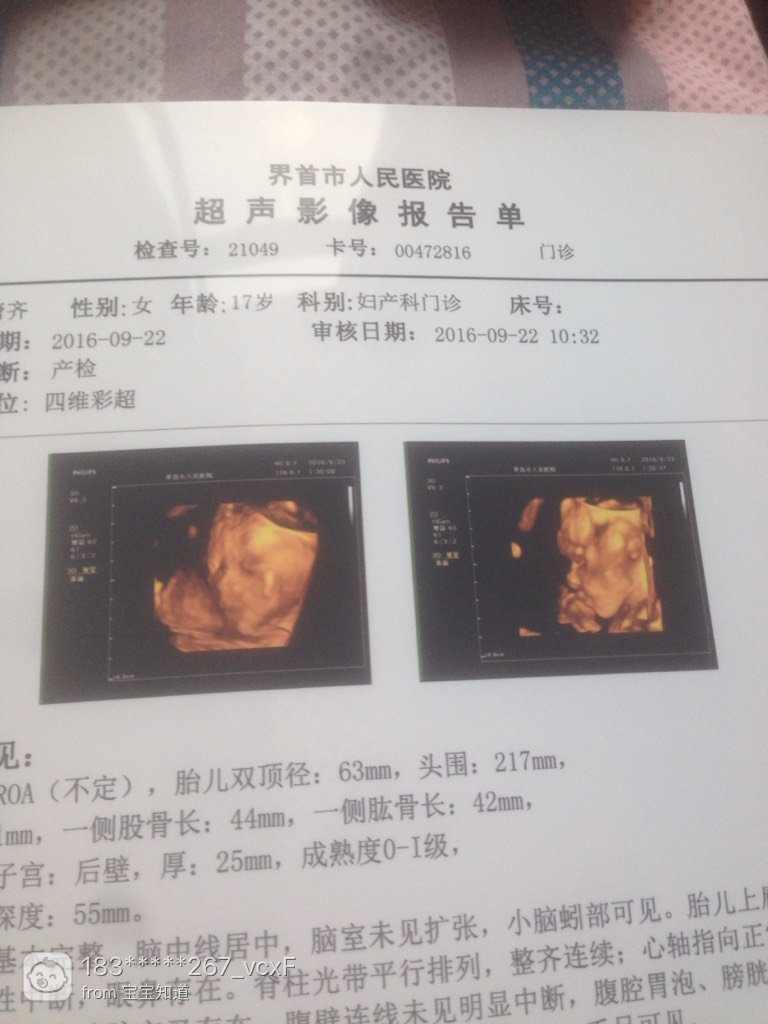

和老公都是圆脸,怎么四维是尖脸

我和他都是圆脸,灿辉怎么看着四维小孩是震遮尖脸呢,第一高布露张是我怀孕之前的照片,第二张是怀孕过后的照片,第三是四维彩超

没人吗?我今年是21!不是十七,身份证上小了两岁

宝宝都是看到一边脸,肯定看着就这样

侧脸都是这样,我是长脸,我家宝宝做4维侧看也是尖的